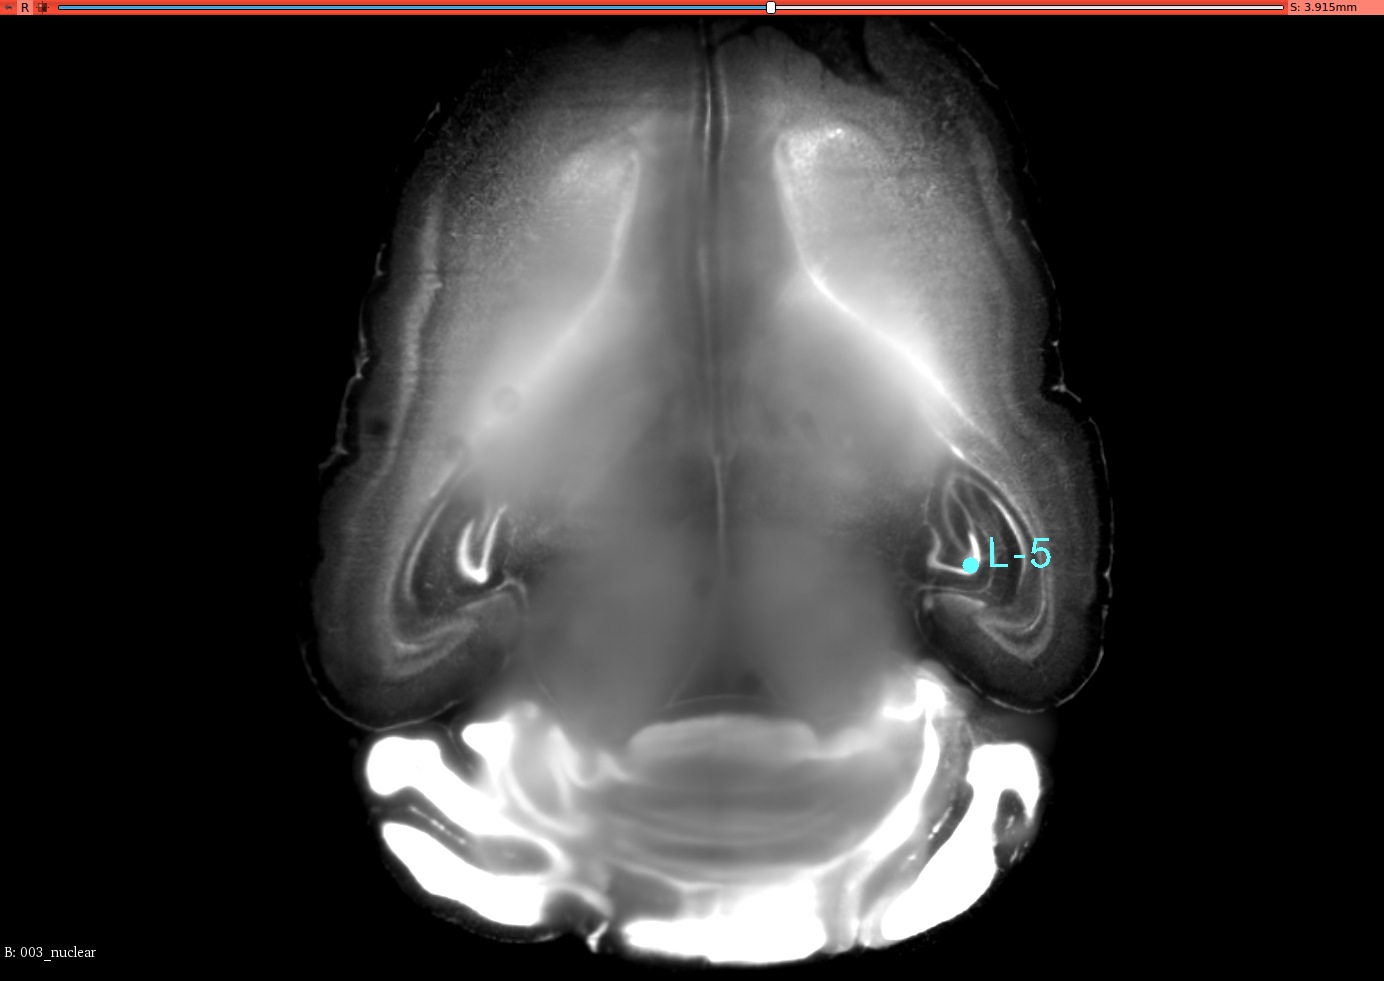

To validate the registration performance of the proposed methods and comparing the baseline methods in a more objective manner, a landmark registration test is conducted. In the CUBIC dataset, three brains are used to test the registration performance. In the landmark test, the same dataset is used for the performance validation. 12 landmarks are selected and all of these landmarks are selected where their positions vary in all three axis. 3D slicer tool is used to select the landmarks for this experiment from the CUBIC brains. A set of selected landmarks are shown in Figure 7. Table 3 shows the results of the 3D landmark registration by proposed InvGAN method and other baseline methods. The Euclidean distance between the registered landmarks and reference landmarks are presented in mm. For optimisation-based ANTS and Elastix tools, the same parameter sets are used to register landmarks selected from moving image and fixed image. After the registration, the output point locations are compared with reference point locations in the fixed image. For the deep-learning-based VoxelMorph and InvGAN, the deformation values in X,Y and Z are extracted from the same voxel location of the selected landmark’s voxel location. After applying deformation to the landmarks, the new position is compared with that of corresponding reference points in the fixed image.

Refer to caption

(a) Brain-1

(b) Segittal View

(c) Coronal View

(d) Corresponding Points in Brain003

(e) Segittal View

(f) Coronal View

(g) Brain-2

(h) Segittal View

(i) Coronal View

(j) Corresponding Points in Brain-3

(k) Segittal View

(l) Coronal View

Figure 7: 3D Landmarks